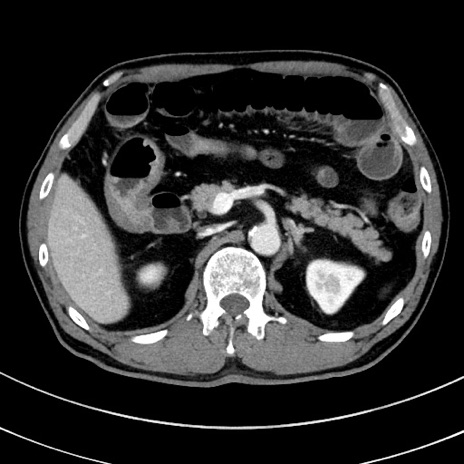

症例8(横断像)

【症例】 60歳代男性

【主訴】 黒色吐物

【現病歴】 4日前から嘔気自覚、2日前の朝食後にも嘔気あり、自分で手で嘔吐反射起こし嘔吐したところ血が混ざっていたため受診。

【既往歴】 5年前汎発性腹膜炎を伴う急性虫垂炎で手術、高血圧、前立腺肥大症、高脂血症

【身体所見】 腹部正中に手術癩痕あり 腹部平坦・軟圧痛なし膨満感あり

【データ】WBC 8400、CRP 4.54